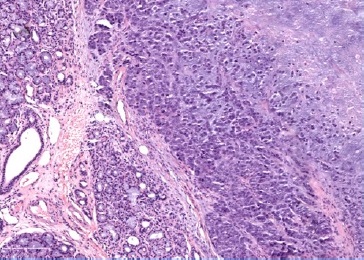

On physical evaluation, a painless 1.2-cm firm nodule was palpable sublingually, leading to the presumptive diagnosis of sialolithiasis. The mass was removed and submitted to pathological examination. Grossly, the lesion was firm and grayish with irregular borders (Figure 2). Histopathology showed a malignant lesion comprising neoplastic epithelial cells arranged in small nests with a large central area of chondroid matrix (Figure 3). The epithelial cells were large, with hyperchromatic and pleomorphic nuclei presenting a high mitotic rate (Figure 4). At the edge of the fragment, salivary parenchyma exhibiting ductal ectasia with scant inflammatory cells was identified.

Figure 3 Periphery of the sublingual lesion, showing sublingual parenchyma (left), and tumor with chondroid matrix (right), HE